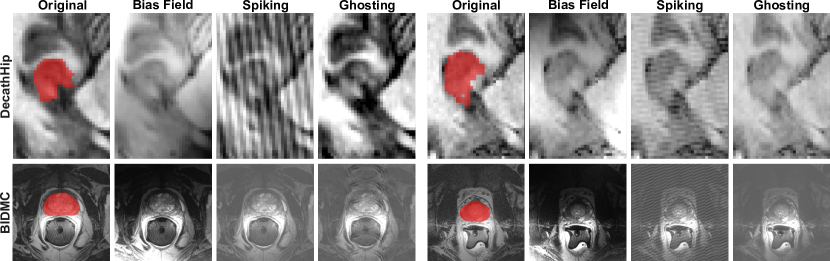

Analysis of Generated Features: Finally, in Figs. 6 we qualitatively support our quantitative findings by visualizing segmentation masks of the train set and similar segmentation masks of the ccVAE’s generated features included in pseudo-rehearsal training. The generated features are semantically coherent, cover multiple volume segments and successfully capture geometric diversity.

Figure 6: Ground truth segmentation masks from the original tasks and segmentation masks from generated features using different slice and task indices.